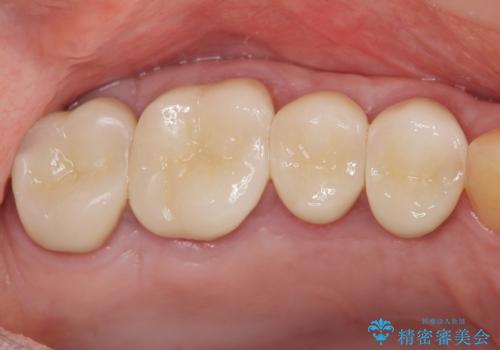

一つ一つの工程を丁寧に行うことで、根尖病変の改善傾向も見られ、安定した歯周環境を整えることができました。